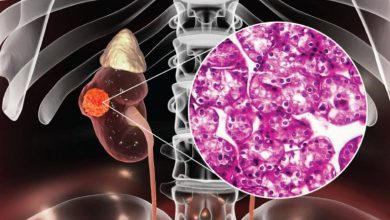

سرطان کلیه چیست و چه علائمی دارد؟

سرطان کلیه چیست و چه علائمی دارد؟ سرطان کلیه رشد غیرطبیعی سلولها در بافت کلیه است. به مرور زمان، این…